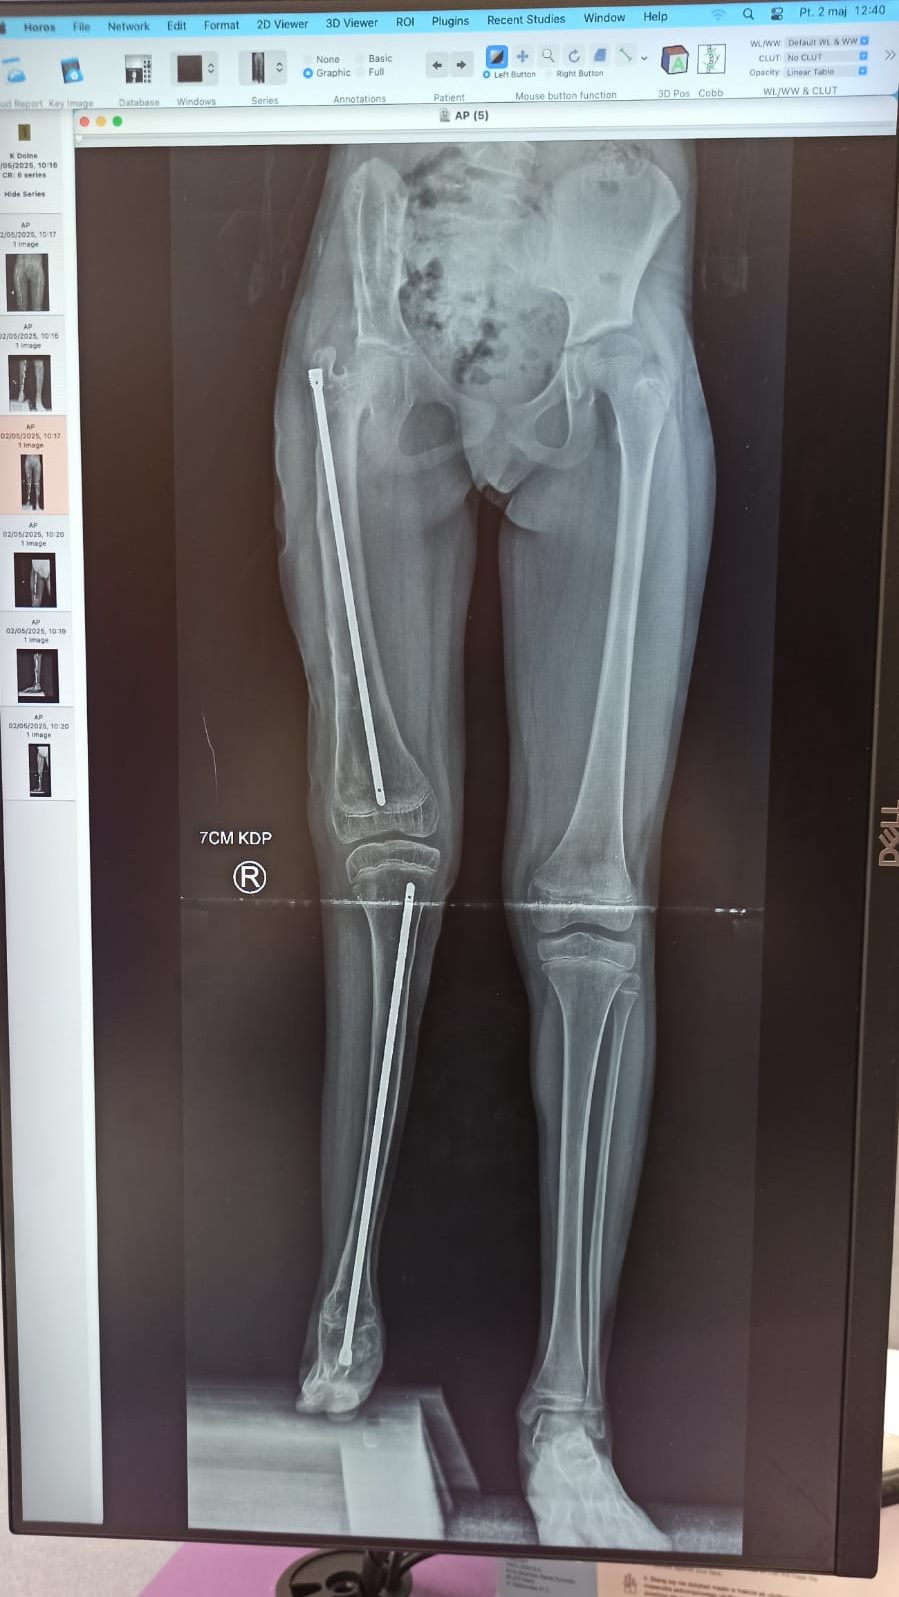

appurati 7 cm di discrepanza tra gli arti di Nicole